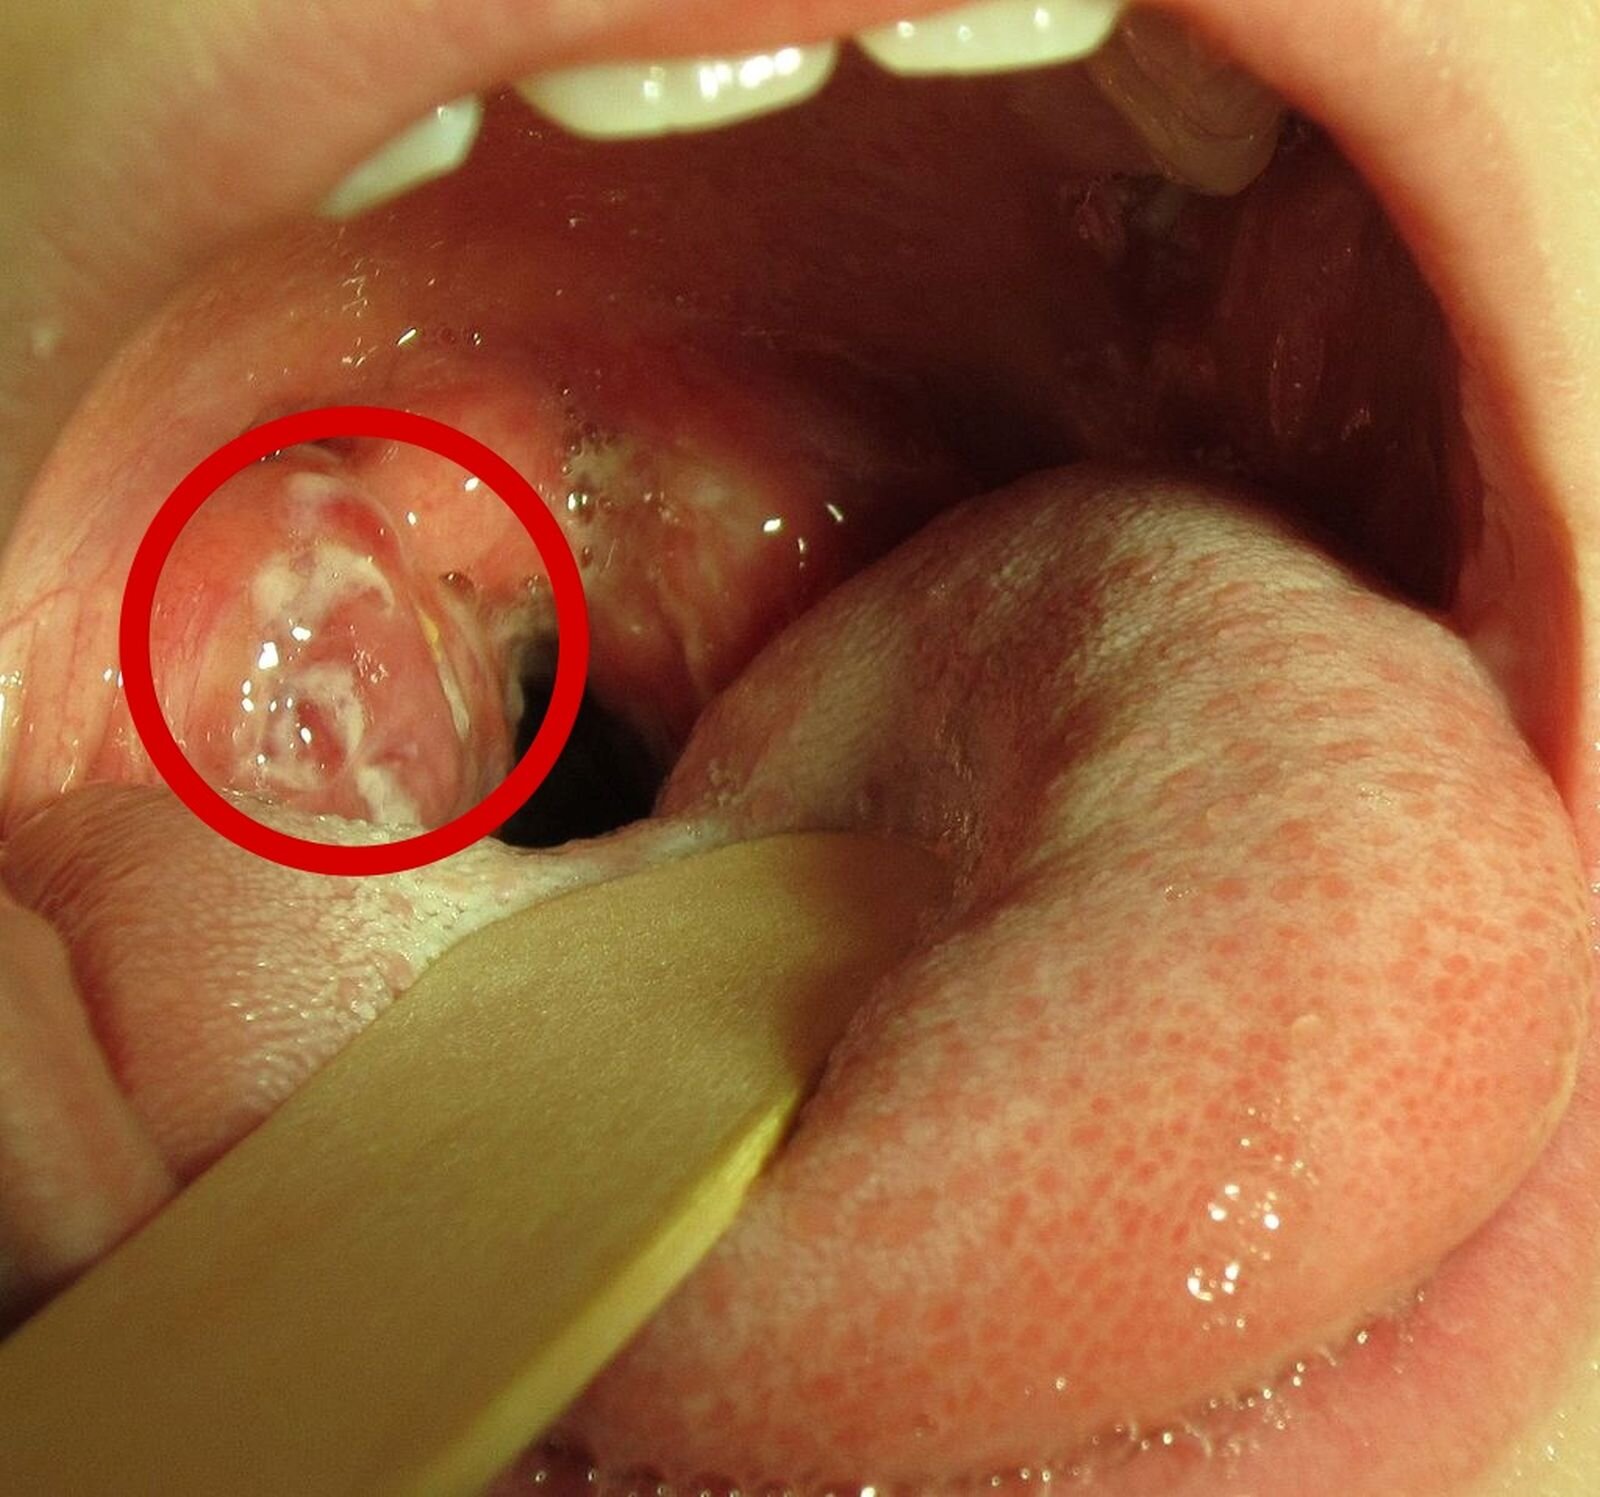

Angina

Angina to ostre zapalenie migdałków i błony śluzowejbłony śluzowej gardła. Objawia się silnym bólem gardła utrudniającym połykanie i mówienie, wysoką gorączką, bólami stawów i złym samopoczuciem.

Migdałki to małe narządy znajdujące się w błonie śluzowejbłonie śluzowej jamy ustnej i gardła. Przyczyniają się do produkcji komórek układu odpornościowego (przeciwciał). Przeciwciała pełnią funkcję ochronną: niszczą lub neutralizują szkodliwe czynniki, np. bakterie, które przenikają przez drogi pokarmowe i oddechowe. Podczas anginy migdałki są zaczerwienione, rozpulchnione i pokryte ropnym nalotem.